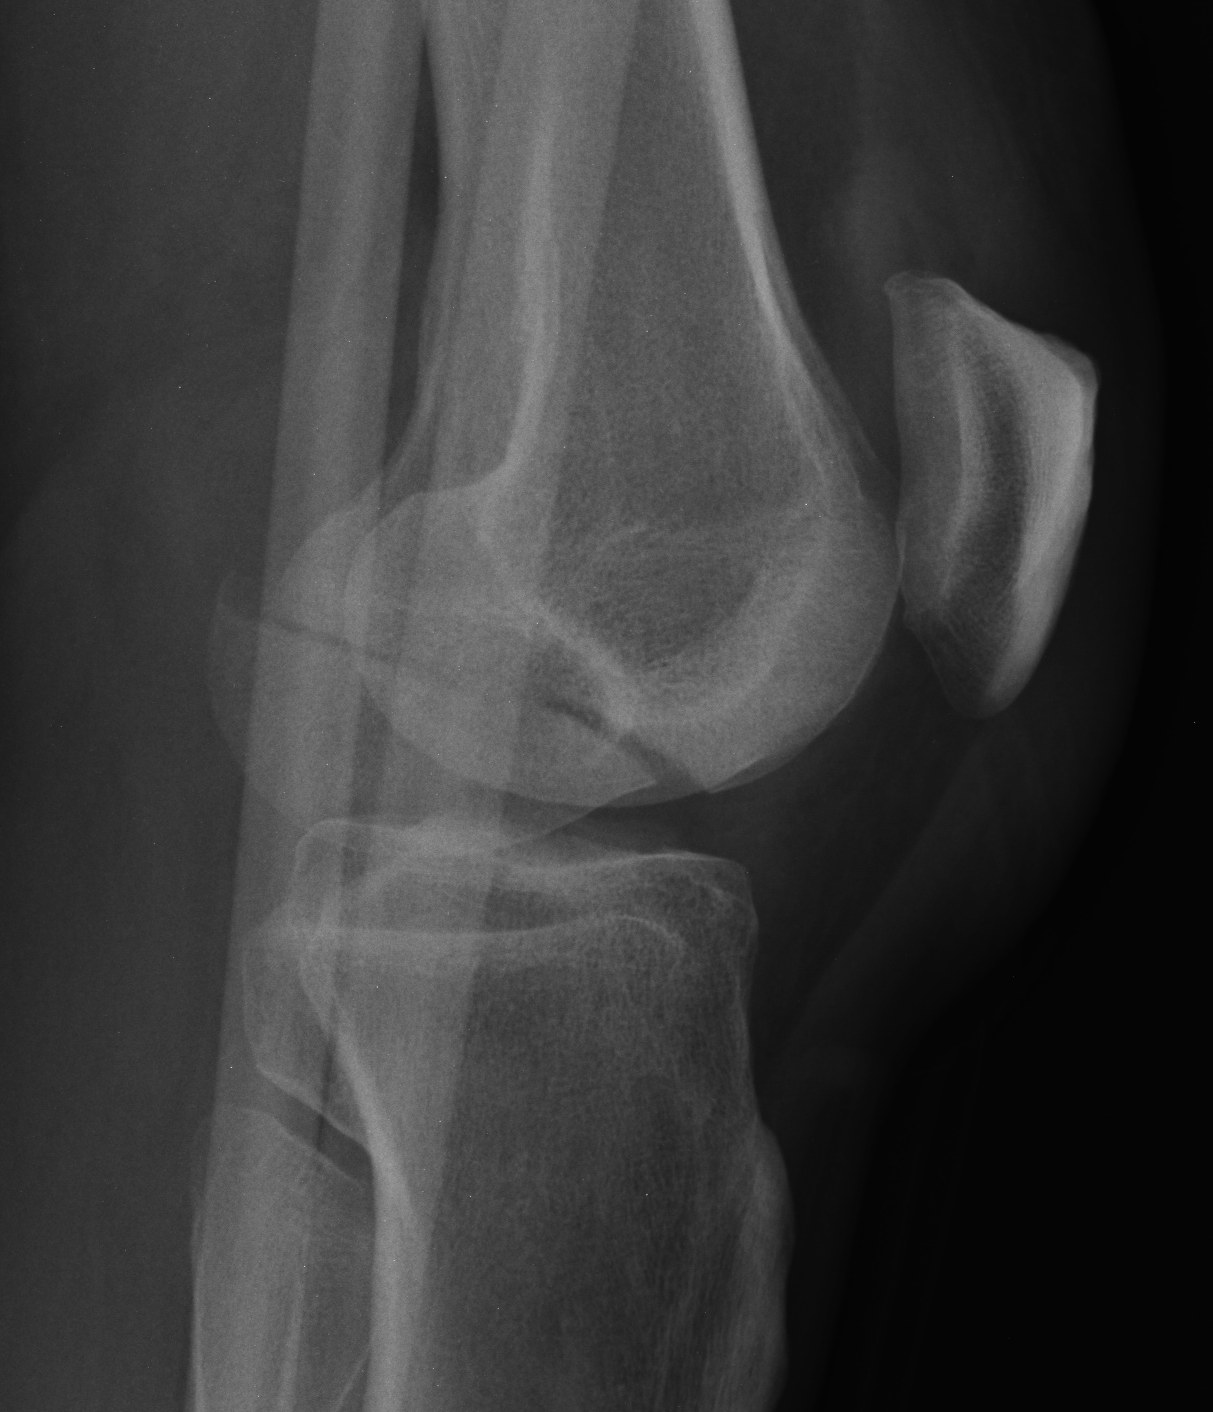

Coronal plane fracture of distal femoral condyle

- intra-articular

- often only attachment is posterior capsule

Rare

Usually a severe valgus trauma